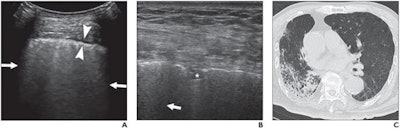

(A) Lung ultrasound image obtained with a convex probe. The outer arrows show confluent B-lines. The middle arrowheads point to a thickened pleural line. (B) Lung ultrasound image obtained with a linear probe. The arrow points to a B-line. The star denotes a patchy pulmonary consolidation. (C) Chest CT image showing reticular and interlobular septal thickening and patchy, focal opacities associated with architectural distortion. Image courtesy of the American Journal of Roentgenology.Furthermore, patients with a thickened pleural line had experienced a longer infection period than those without a thickened pleural line. Patients with fewer than 20 days between the day they first noticed COVID-19 symptoms and the day of their ultrasound scan were significantly less likely to have a thickened pleural line than those with a difference of 20 days or more.

Every patient in the study had B-lines on their ultrasound scans, which indicate areas of increased interstitial fluids and decreased alveolar air. Another two-thirds of patients had pulmonary consolidation, and 61% had a thickened pleural line. Only one patient had a pleural effusion.

Pulmonary consolidation occurred significantly more often in patients with severe or critical COVID-19 than patients with moderate disease, the authors found. Almost 87% of patients with severe or critical disease had pulmonary consolidation on ultrasound, compared with just 46% of patients with moderate COVID-19.